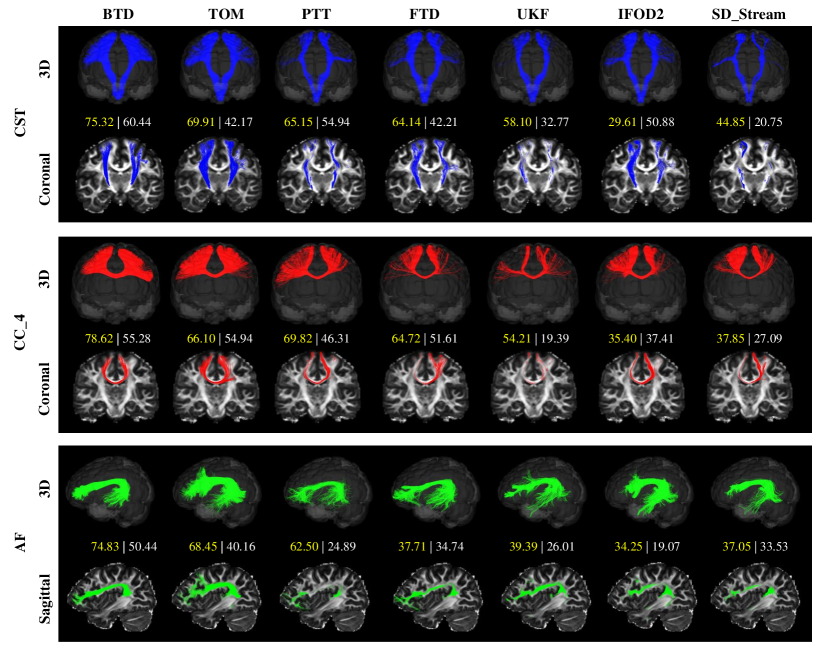

Refer to caption

Figure 9: Qualitative comparison of tractography results reconstruction of CST, CC_4, and AF on HCP #100307 subject. Top: the 3D display of tracked fiber bundles. Bottom: the slice display of tracked fiber bundles on the FA images. Middle: the quantitative comparison of different tractography methods with tractometer metrics (VC(%) ||| OL(%)).

We used HCP #100307 subject to visually compare fiber tractograms from the proposed BTD algorithm and results from the tract orientation mapping (TOM) [57], parallel transport tractography (PTT) [33], fiber trajectory distribution (FTD) [34], unscented Kalman filter (UKF) algorithm [52], integration over fiber orientation distributions (iFOD2) [51], and deterministic FOD-based tracking (SD_Stream) [50]. In this paper, we use VC and OL to validate the proposed method, so all tractography methods were selected 3000 streamlines which were seeded from all voxels within the each tract start regions, and tract masks were used to filter the tractograms. The tractography specific parameters are as follows: i) FTD, iFOD2, and SD_Stream: maximum angle = 600superscript60060^{0}, step size = 0.3, cutoff = 0.1, minimum length = 75; ii) UKF: seedingFA = 0.06, stoppingFA = 0.05, stoppingThreshold = 0.06, Qm = 0.001, and Ql = 50. iii) PTT: the default parameters in [33], the difference is that the seeding regions are the tract start regions. iv) TOM: the default parameters in [57], the difference is that the seeding regions are the tract start regions, max_nr_fibers=3000, no streamline filtering by end mask.

In the absence of ground truth fibers for in vivo data, the relatively familiar corpus callosum (CC_4), CST, and arcuate fasciculus (AF) were selected for qualitative and quantitative evaluations. The AF is a neuronal pathway that connects Wernicke’s area and Broca’s area [58]. The CC_4 is minor forceps of the corpus callosum that connects bilateral frontal lobe [59]. These three tracts have the characteristics of long-range, twisting, and fanning characteristics, making them suitable to assess the algorithms.

The main lost fibers in the TOM, PTT, FTD, UKF, iFOD2, and SD_Stream are mainly distributed in fanning and other complex geometric structures, such as the fibers ending in area 4tl and 4hf of precentral gyrus (CST), frontal lobe on CC_4 and temporal lobes on AF. The results are consistent with VC and OL in middle of Fig. 9, in which the BTD obtains highest VC and OL. We also exhibited the fibers of AF and CC_4 on anatomical slices in top of Fig. 9 (the slices and fibers of CC_4 can be seen in bottom of Fig. 9). In addition, the BTD of 7th-order or higher may overfit in the termination region.

In addition, we also give tractometer metrics results of the proposed BTD on CST using five HCP data (subject ID: #100307, #112112, #112920, #113821, #118831) in Fig. 10. The results show that the proposed method is higher than the other compared methods in VC and OL tractometer metrics. We can also see that BTD has a significant improvement compared to FTD, which illustrates the advantage of BTD for complex bundle reconstruction by establishing higher-order streamline differential equations at the global level.